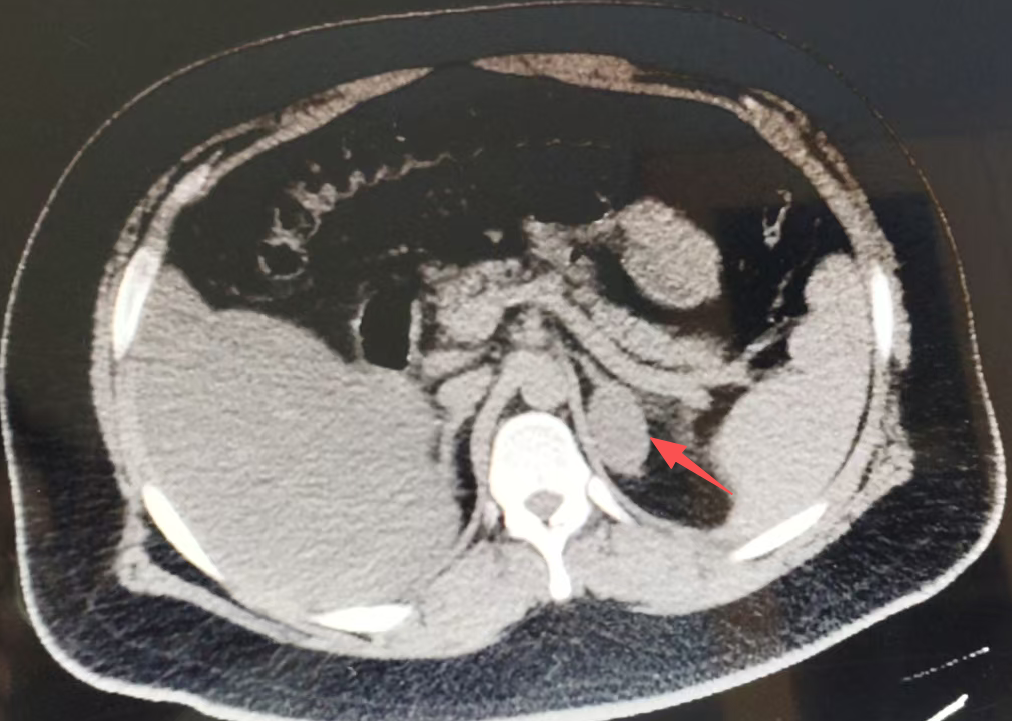

一旦生化检查提示异常,下一步就是通过影像学检查(如肾上腺专用CT或MRI,我院已开展)来定位“肇事”的肿瘤或增生部位。明确了病因和病灶位置,治疗就有了清晰的方向。

(图片资料来源于临床)